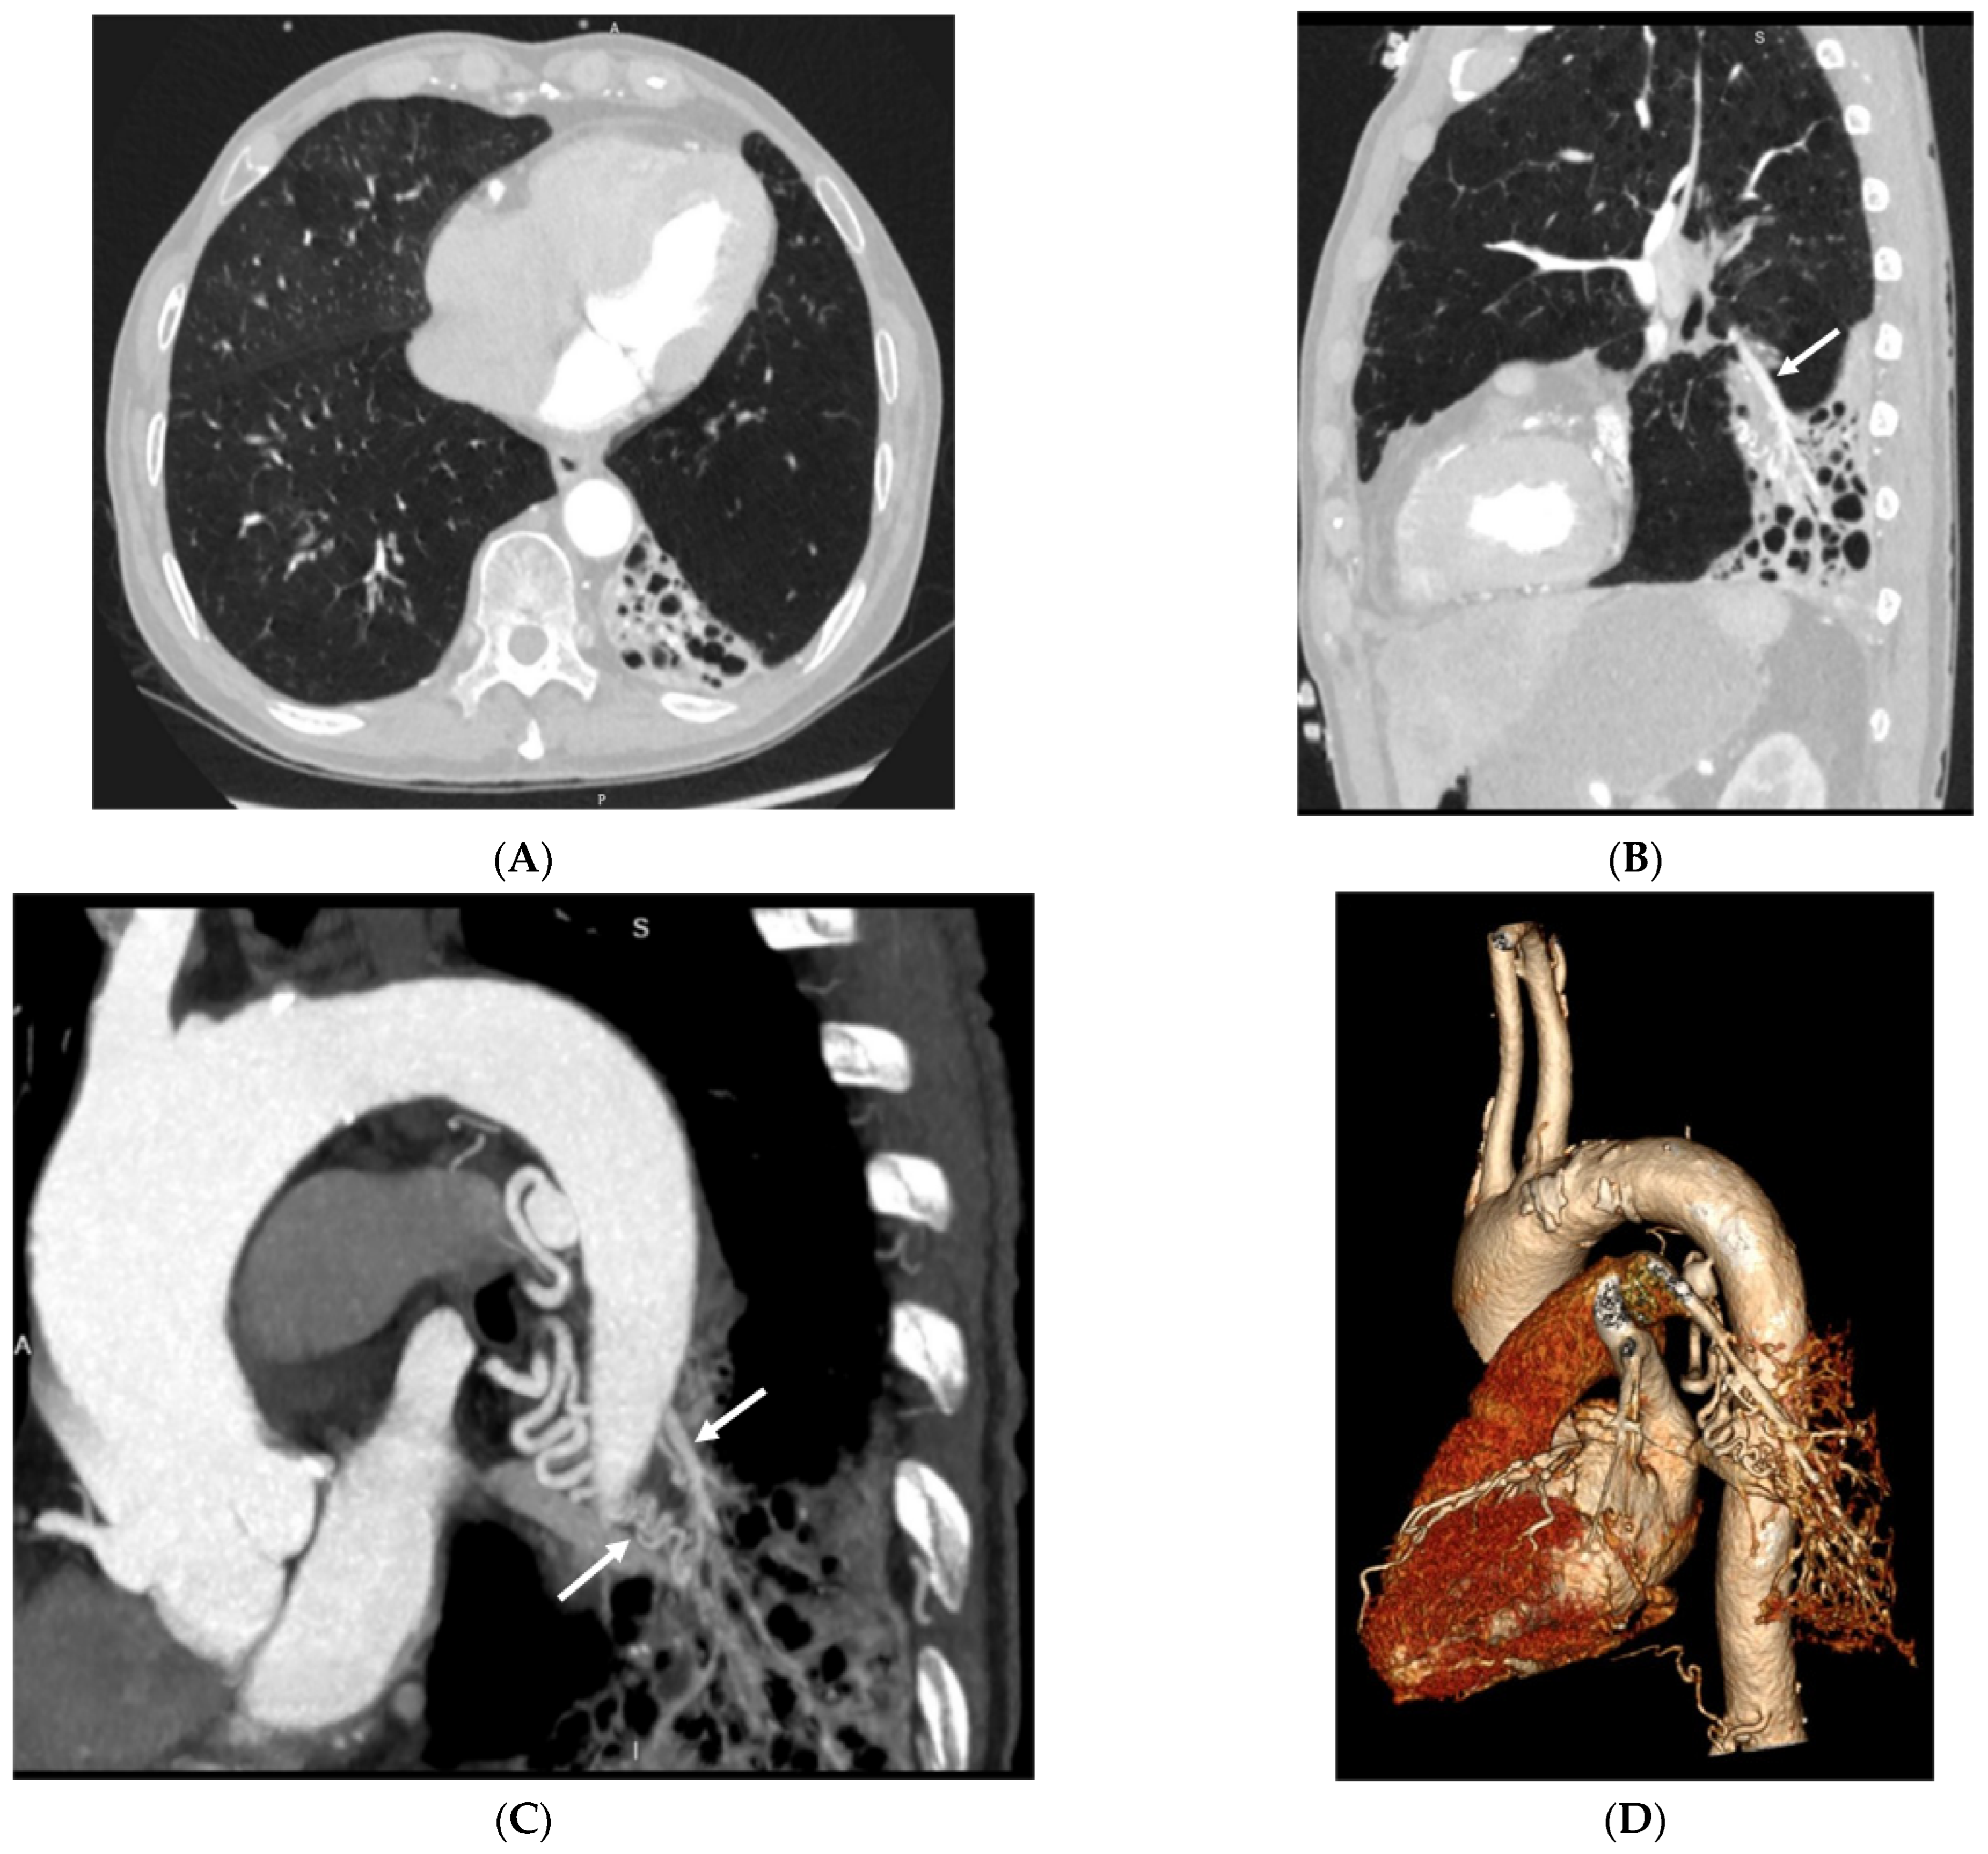

3.2. Imaging Appearances of CTPA